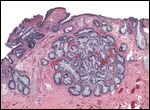

FIGURE 1

Specimen #1-

Histologic examination of a 3-year-old cystectomy specimen showed extensive proliferation of glands in the lamina propria (H&E, 4x objective).

Dr. Francisco La Rosa: We reviewed for second opinion diagnosis the outside surgical pathology case established for this patient, consisting of a urinary bladder biopsy and a cystectomy specimen from 3 years ago. Histologic examination of the cystectomy specimen showed extensive proliferation of glands in the lamina propria (Figure 1), which were lined by columnar epithelium, including goblet cells and Paneth cells (Figure 2). Some sections showed pools of mucinous material with extravasation into the stroma (Figure 3).